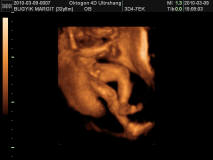

Megvolt az Uh és doktornő uh-on megint rendben talált mindent. Olyan kis édes volt. Kivételesen aludt, felébredt, elaludt. Nem volt akkora ugra-bugra most.

Kitaláljátok a nemét? :lol: